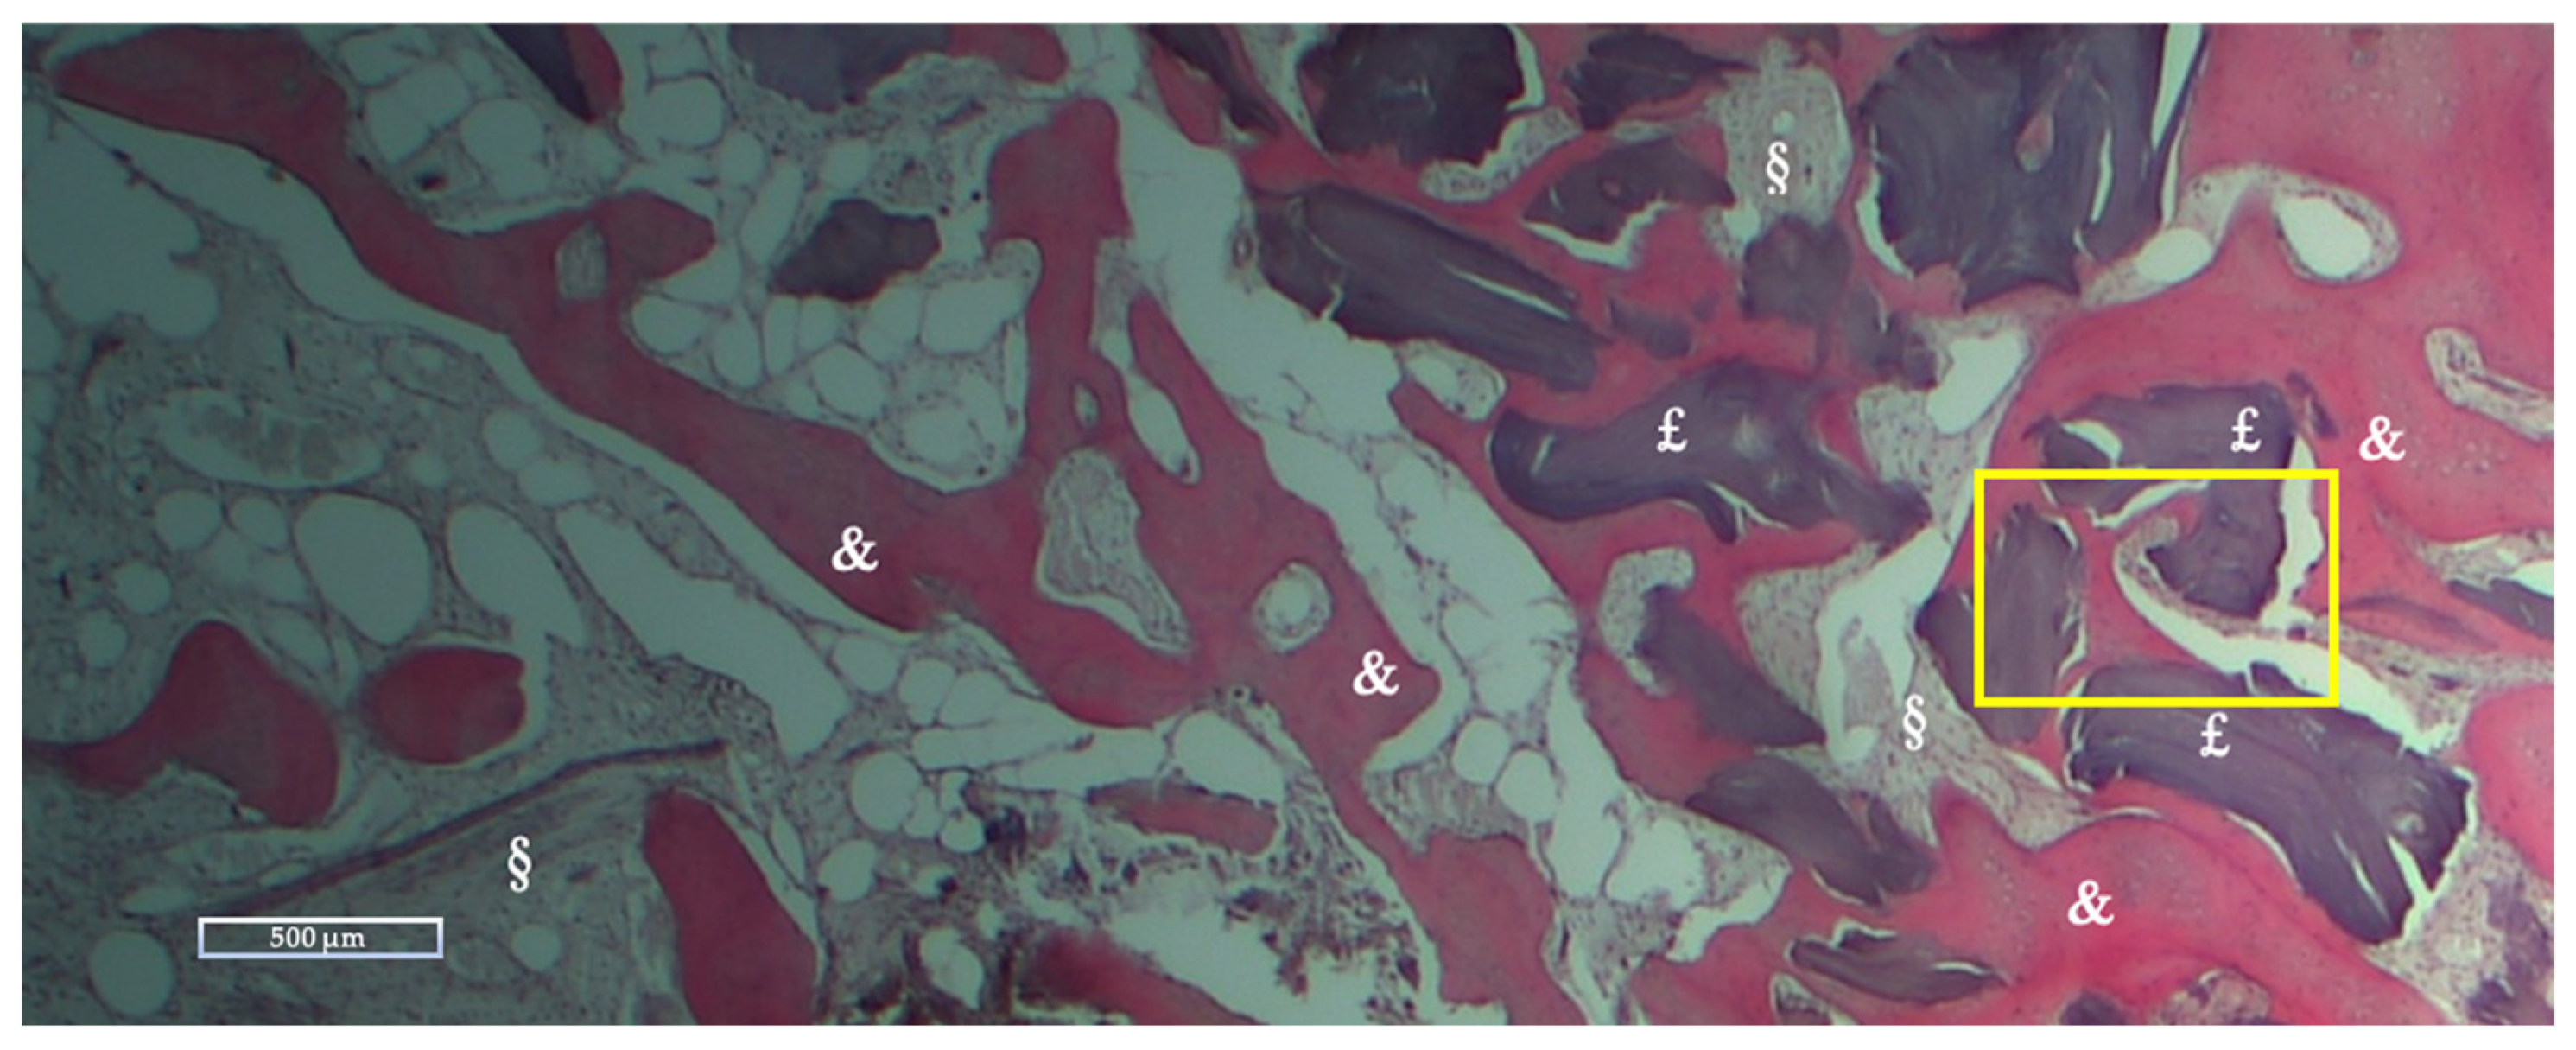

| NFB | RB | SF | |

|---|---|---|---|

| Mean % ± Std dev | 28.27 ± 10.62 | 10.39 ± 12.01 | 61.33 ± 12.08 |

| Range % (Min-Max) | 16.51–59.74 | 0–36.89 | 40.26–75.59 |